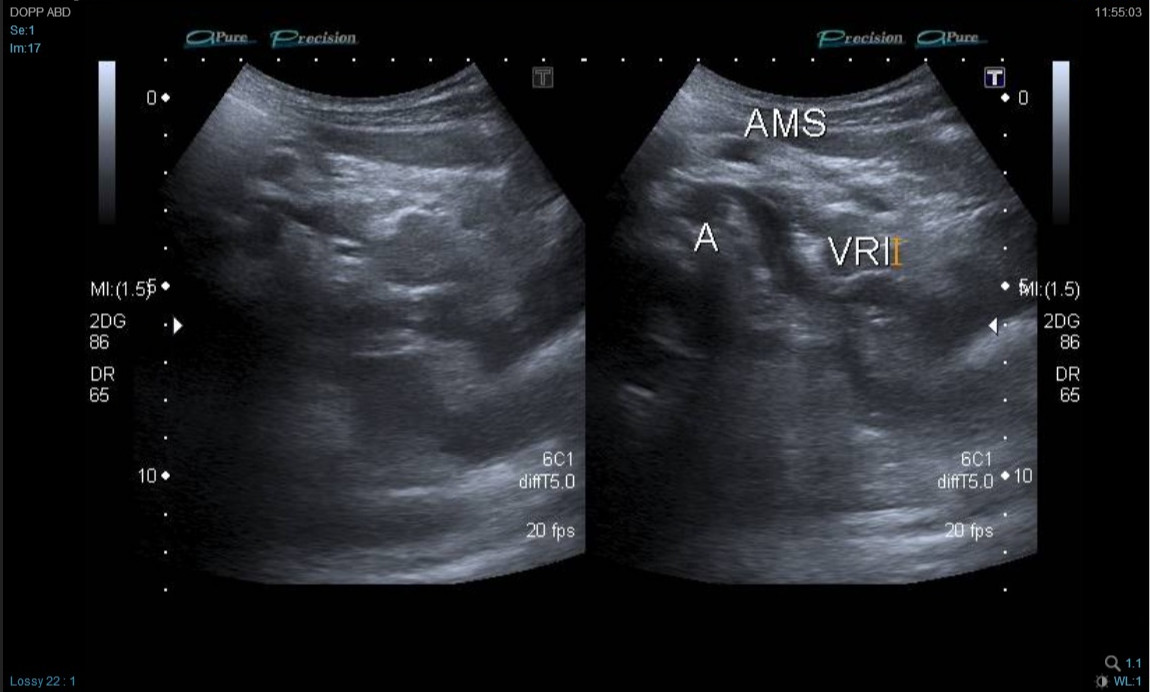

Por la edad del paciente (por evitar la irradiación) y la sospecha clínica, se decidió realizar primero nueva ecografía Doppler (Fig. 1) por personal experto y dirigida con la sospecha de síndrome del cascanueces, observándose una mínima dilatación de la vena renal izquierda en su salida y provocada posiblemente por la salida de la arteria mesentérica superior (pinza aortomesentérica). Se identificó también una disminución de la velocidad con respecto a la vena renal derecha. Estos hallazgos confirmaron la sospecha clínica de síndrome del cascanueces por compresión de vena renal izquierda por pinza aortomesentérica.

Figura 1. Imagen ecografía Doppler. Mínima dilatación de la vena renal izquierda en su salida, provocada posiblemente por la salida de la arteria mesentérica superior (pinza aortomesentérica)